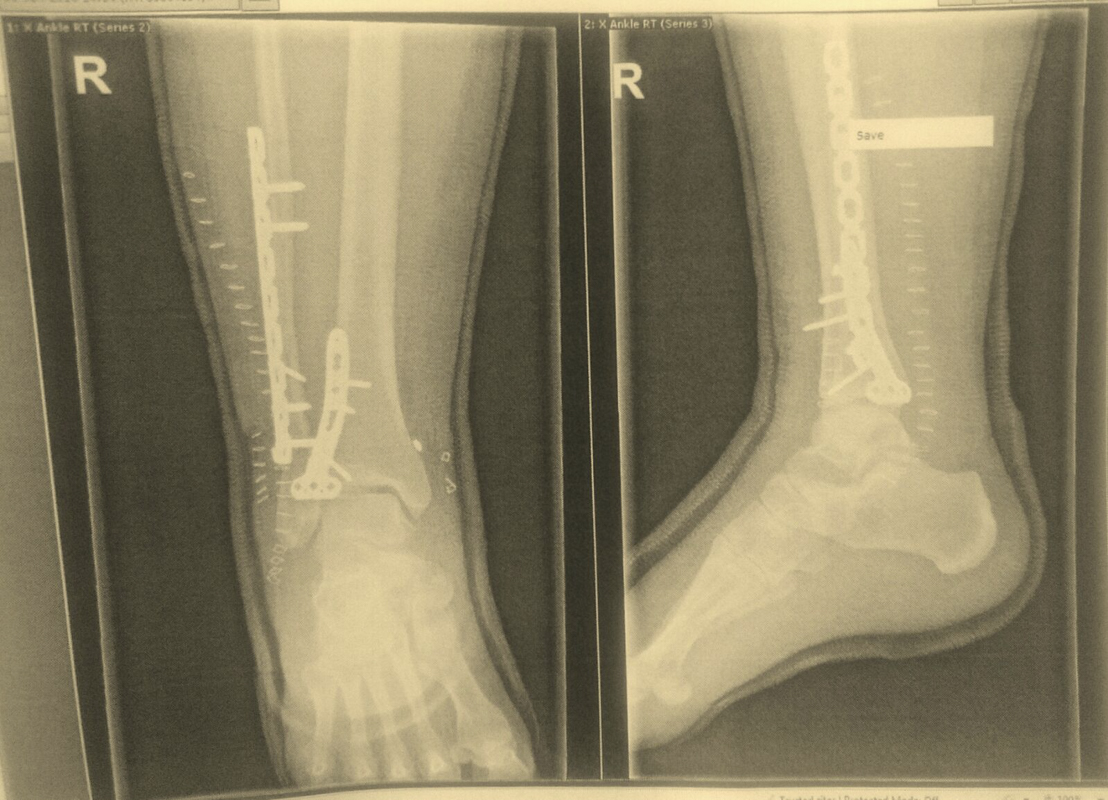

Picture those faces people pull when they see something horrendous….that was what the radiographer and the two doctors who came in whilst I was being X-rayed pulled. Erm, excuse me, I am here you know, and you’re not making me feel any better about this! I think the shock had hidden from me how bad it was, obviously I knew it was bad, but not that bad. I thought they’d see this kind of thing regularly but apparently I won the best X-ray for the week! Cheers!

They let me look at the X-ray and that’s when I realised I had done a good job. Well if you’re going to do something, then do it properly, hey? I spiral fractured the fibula, a clean break on the tibula and just to top things off, dislocated my ankle, snapping all the ligaments on the way. My ankle had now been out of place for a good seven hours and the skin was going opaque from being pushed so hard for so long.

I went for surgery at 9:30am, and came out at 6pm. Oh my life… I have never felt pain like it! I now have that number 10 on the scale to compare future pain to and I never want to go there again. I like to think I have a high pain threshold too. What had they done to me?! I’d been cut open a good eight inches and had two plates, a number of screws to hold them into place, and two new ligaments, topped off by 38 staples! Ouchhhhhhhh ouch ouch! Though to my relief I could see no metal outside my body.